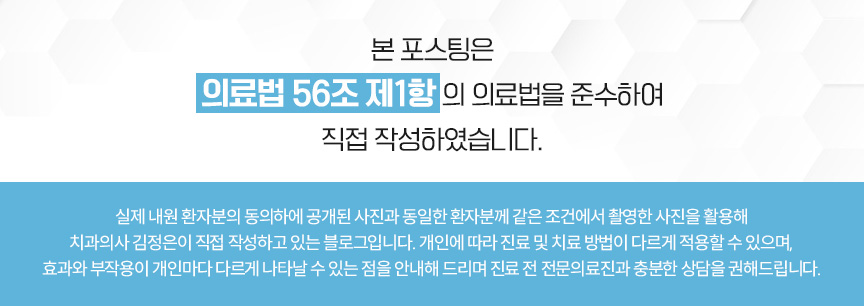

구강 내 모습을 보았을 때

위아래 턱 모두 좁은 악궁을

가지고 있는 것을 확인할 수 있었는데요.